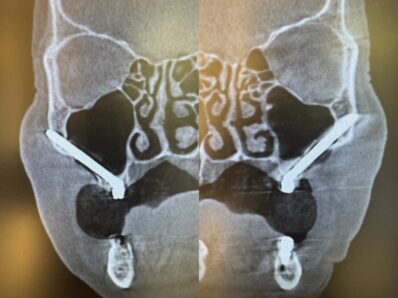

今回は10年以上前に行われた全顎のインプラントが弱ってしまいお痛みの主訴で来院された患者さん。

ザイゴマにてリカバリーを行う症例でした。上顎を4本のザイゴマインプラントで治す予定でしたが、ギリギリ前歯が使えたため上を5本、下顎を4本のインプラントを用いて即日で治療しました。